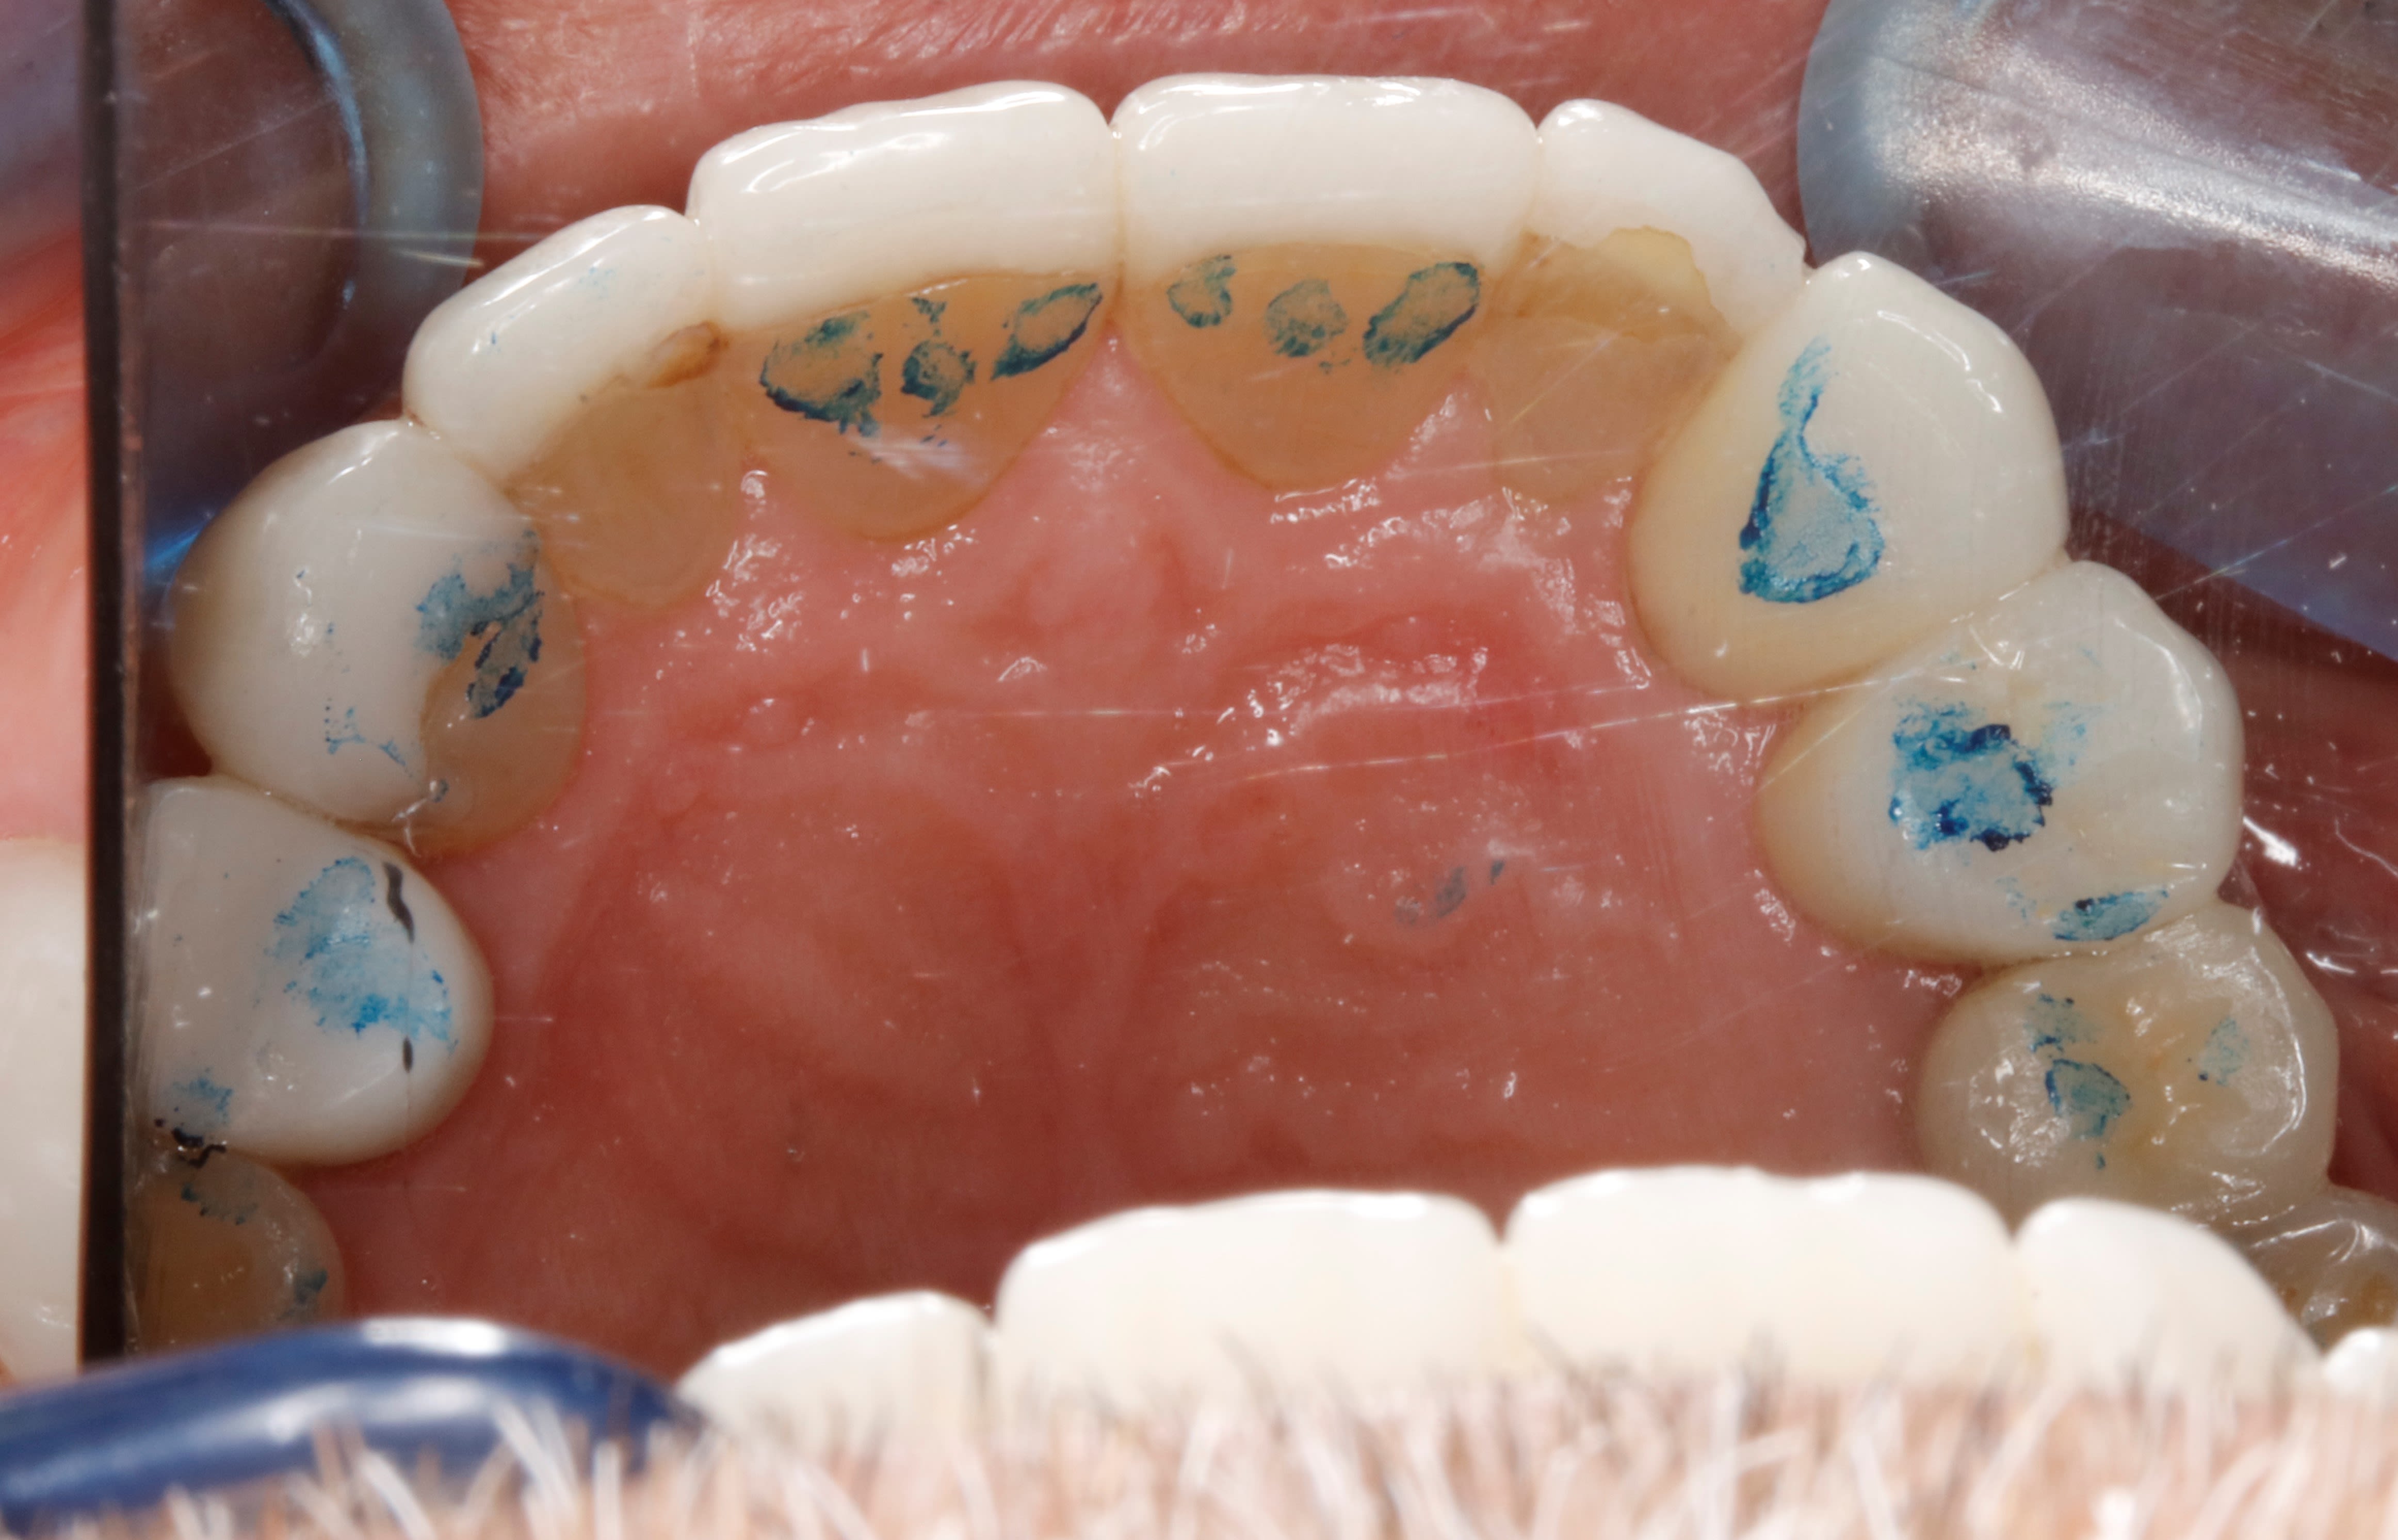

le bridge du haut vue occlusale

mg 1947 kffz5n - Eugenol